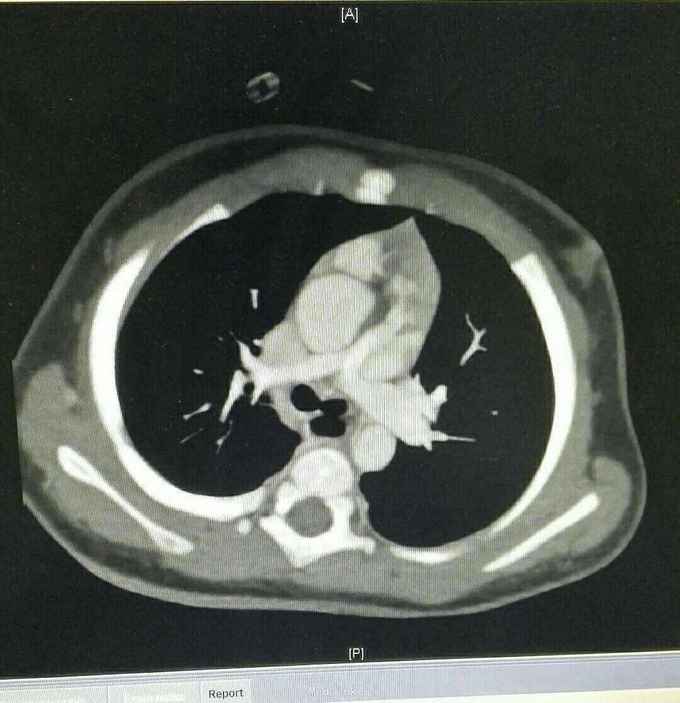

查体 生命体征平稳,口唇发绀,双肺呼吸音清,未闻及干湿性罗音,心律规整,于胸骨左缘可闻及杂音,腹部平软无压痛反跳痛,双下肢无水肿。 辅助检查结果 心脏彩超示 先天性心脏病 法乐氏四联症 肺动脉发育不良 左肺动脉 0.65mm,右肺动脉 0.49mm。 心脏CT检查结果示 先天性心脏病 法乐氏四联症 肺动脉发育不良

先天性心脏病 法乐氏四联症 治疗 患者入院后完善各项术前检查及准备,排除手术禁忌症后为患儿行跟手术治疗。 手术过程 全麻成功后,常规消毒,胸骨正中切口,常规建立体外循环,降温阻断升主动脉后,心脏停跳,切开右房,经卵圆孔放置左心引流,经右心室流出道切口,切除肥厚的隔束及壁束,切开肺动脉瓣交界处粘连,可通过9号探子,左右肺动脉可通过7号探子,取涤纶补片修补室间隔缺损,已带瓣牛心包补片加宽右室流出道,开放循环,心脏复跳,手术过程顺利,患者安反监护室。